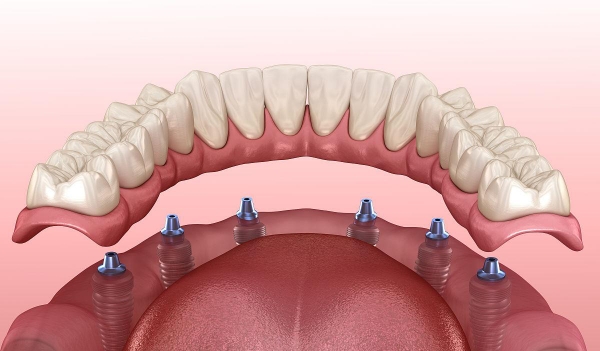

值得注意的是,60歲以上老年患者憑有效身份證件可享受種植牙項(xiàng)目9折優(yōu)惠,同時(shí)醫(yī)院還提供分多次付款服務(wù),減輕患者經(jīng)濟(jì)壓力。對(duì)于全口或半口牙缺失患者,醫(yī)院推出All - on - 4等綜合治療方案,價(jià)格16990元起,相比單顆種植可節(jié)省約30%費(fèi)用。